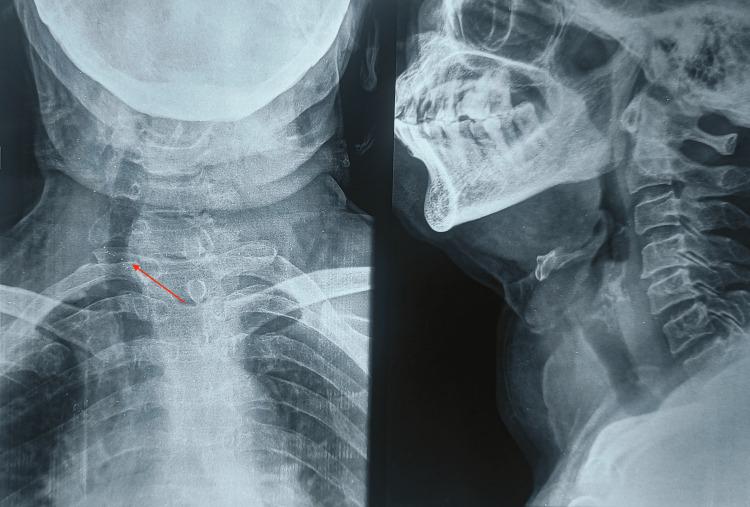

The incidence of mixed thyroid carcinoma of poorly differentiated thyroid carcinoma (PDTC) and papillary carcinoma thyroid is very unusual. PDTC exhibits a high degree of dedifferentiation and histopathological confirmation is done based on Turin's criteria. This type of carcinoma has a poor prognosis and the survival rates at five and ten years post-diagnosis are significantly lower compared to well-differentiated thyroid carcinomas. Surgery is the best mode of treatment at present. This is a case of a 71-year-old female who underwent total thyroidectomy with modified radical neck dissection which yielded a histopathological variant comprising PDTC and papillary thyroid carcinoma. The patient was followed up with a serial thyroglobulin antibody test and ultrasound of the neck at six months and one year, and both were found to be normal.

摘要

低分化甲状腺癌(PDTC)与甲状腺乳头状癌混合性甲状腺癌的发病率非常罕见。PDTC表现出高度的去分化,组织病理学诊断依据都灵标准进行。这种类型的癌预后较差,与高分化甲状腺癌相比,诊断后5年和10年的生存率显著降低。目前手术是最佳治疗方式。这是一例71岁女性患者,接受了全甲状腺切除术及改良根治性颈清扫术,术后病理结果为PDTC与甲状腺乳头状癌的组织病理学变异型。对该患者在术后6个月和1年进行了系列甲状腺球蛋白抗体检测及颈部超声检查进行随访,结果均正常。